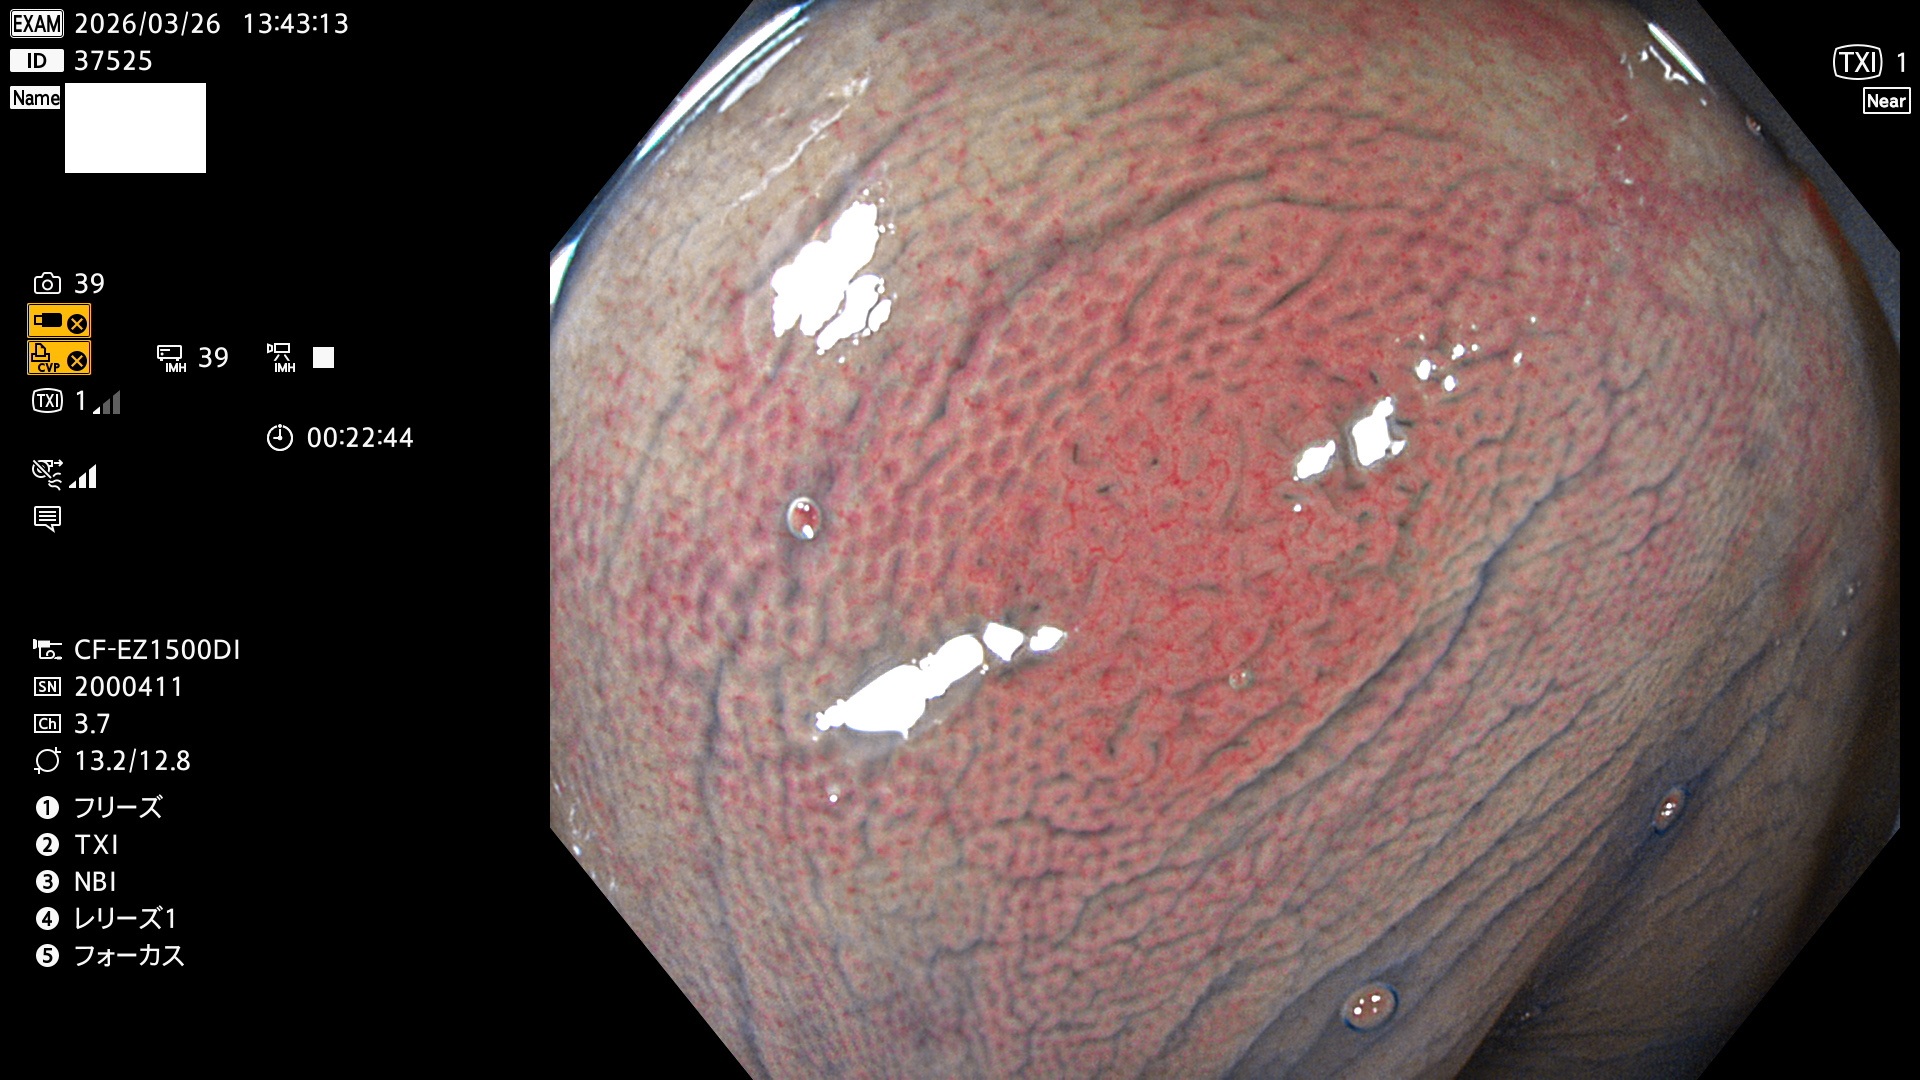

毎週の検査(木・金・土・日)に発見されたUbとUc型・腺腫を、その週の日曜の夜にUPし1週間、提示します。

2026年3月26日〜3月29日の4日間(40件)4個 (Uc_ADR=4個/40人=10%)